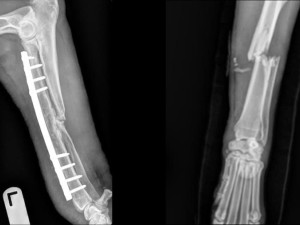

病例分享:以 ARCIS® 固定系統處置之高難度骨折修復骨折型態 橈尺骨骨幹中段/開放性(Grade II)/粉碎性骨折🐕 病患資料 4 歲已絕育公德國狼犬,40 kg(肥胖)。車禍後出現左前肢嚴重橈尺骨骨折。此案同時存在就診延遲、開放性傷口(Grade II)、高度粉碎,以及肥胖造成的行動限制等多重挑戰。👉 臨床挑戰 因肺挫傷與飼主決策,手術延後 4 天 既往過敏性皮膚病史並合併多處擦傷 肥胖導致三足承重困難、增加患肢即刻負重需求 多重因素疊加之感染風險上升 🏥 手術方式 主刀..